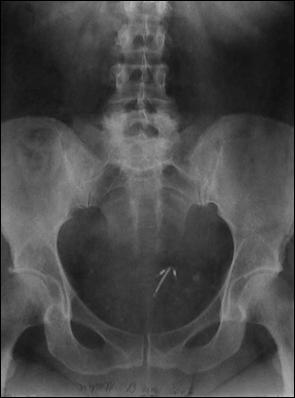

b). Fir de nylon intravezical

Figura 62. Nod din fir de nylon.

c) Sterilet migrat intravezical, complicat cu hematurie

a. b.

c.

a) Ecografie vezicala, evidentiind steriletul migrat intravezical; b) RRVS la aceiasi pacienta; c) Steriletul dupa extractie prin cistoscopie.